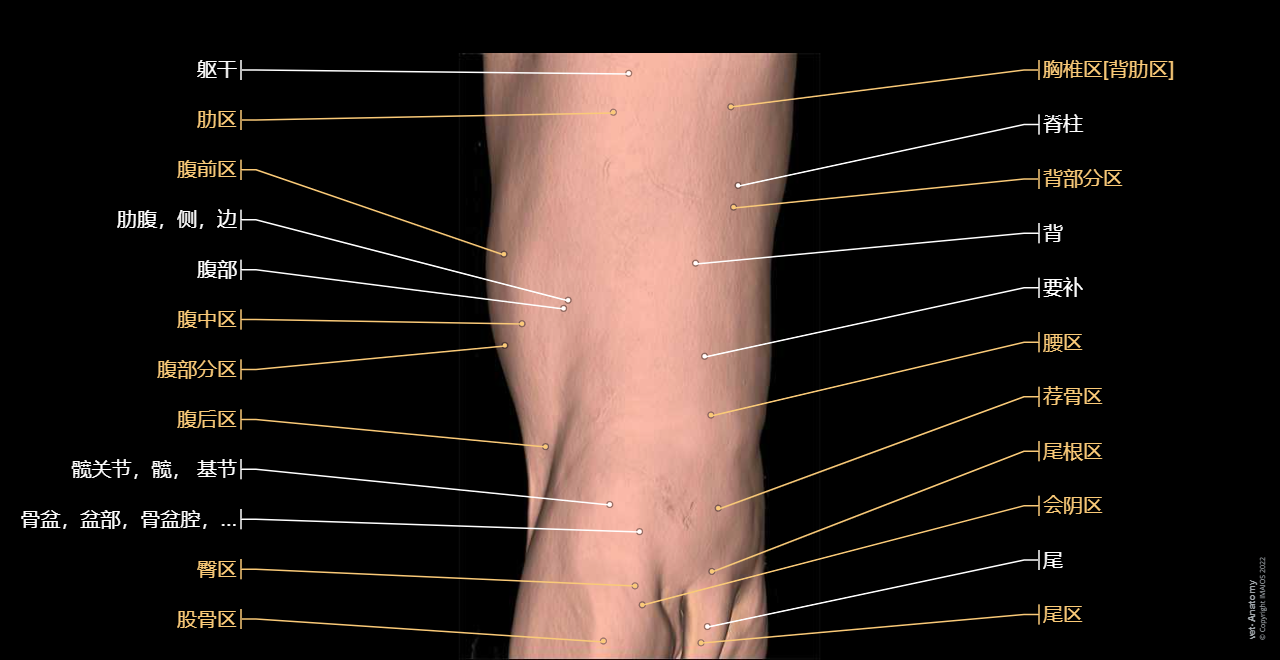

vet-Anatomy兽医图集的本模块是关于CT扫描的犬类腹部和骨盆。

CT图像来自一只健康的6岁阉割雄性犬。

在vet-Anatomy动物图集的此模块中,计算机断层扫描(CT)显示了标有解剖结构的犬科腹腔和骨盆横截面,并用3D图像显示犬科腹部。

CT图像存在3个平面方向(横向,矢状和背侧),并且使用两种对照方式(软组织/血管和骨骼)展现。本模块的末尾提供其他3D解剖图像,便于进一步了解犬科总体解剖结构,展示了骨骼、内脏(肝脏、脾脏、胰腺、消化道)、泌尿生殖系统、动脉、全身静脉系统(主要是尾腔静脉及其分支)、门静脉系统、肌肉和表面解剖的三维容积透视图。

Surface anatomy - 3D: Trunk (Dog)

Surface anatomy